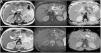

La pancreatitis aguda es una patología común y potencialmente grave que tiene un curso clínico muy variable. Este artículo pretende revisar el papel de las distintas técnicas de imagen en el manejo de esta entidad, describir sus principales manifestaciones radiológicas y la nomenclatura específica asociada a esta entidad.

Acute pancreatitis is common; the clinical course of this potentially severe condition varies widely. This paper aims to review the role of different imaging techniques in the management of acute pancreatitis, describe the main imaging findings for this entity, and explain the terms and criteria used to classify them.